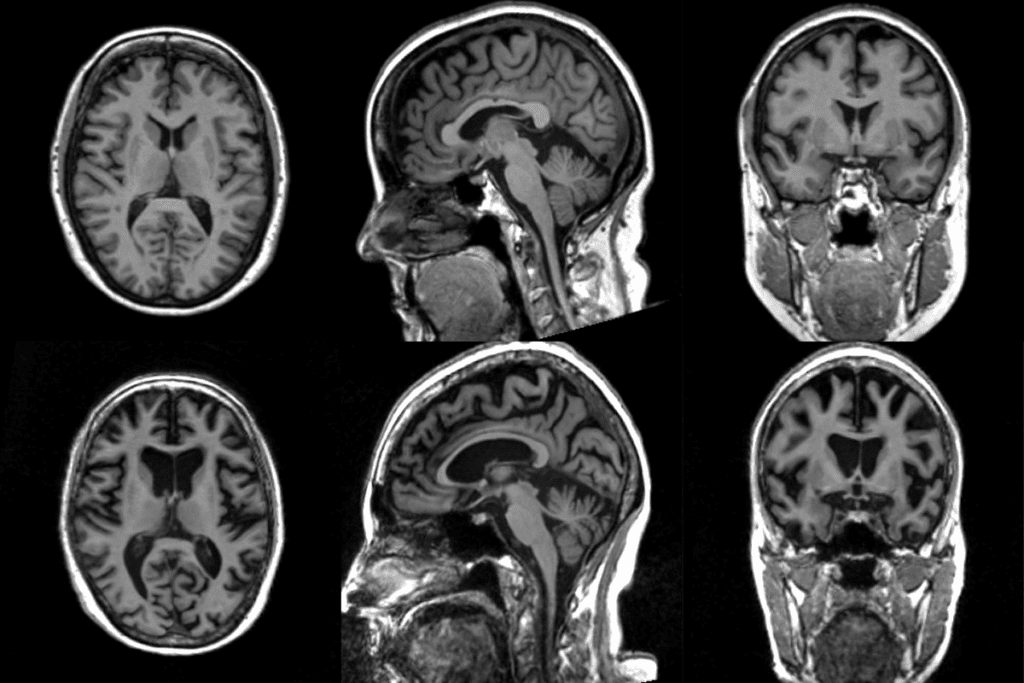

Before starting, patients go through many steps to ensure safety and success. This includes a full medical check-up, imaging tests like angiography or MRI, and talks with our neurovascular experts. They discuss the procedure’s risks and benefits.

- Imaging studies (e.g., angiography, MRI)